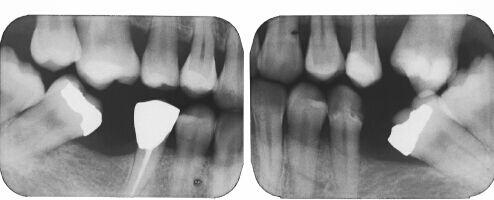

What is wrong here?

There could be many things wrong, but the thing

that I am choosing to focus on is the missing teeth.

This is an x-ray of someone that had back teeth extracted.

This shows the teeth further back tipping into the open spaces.